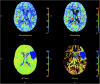

Standard imaging in acute stroke is undertaken with the aim of diagnosing the underlying cause and excluding stroke mimics. In the presence of ischaemic stroke, imaging is also needed to assess patient suitability for treatment with intravenous thrombolysis. Non-contrast CT is predominantly used, but MRI can also exclude any contraindications to thrombolysis treatment. Advanced stroke imaging such as CT and MR angiography and perfusion imaging are increasingly used in an acute setting. In this review, we discuss the evidence for the application of these advanced techniques in the imaging of acute stroke.